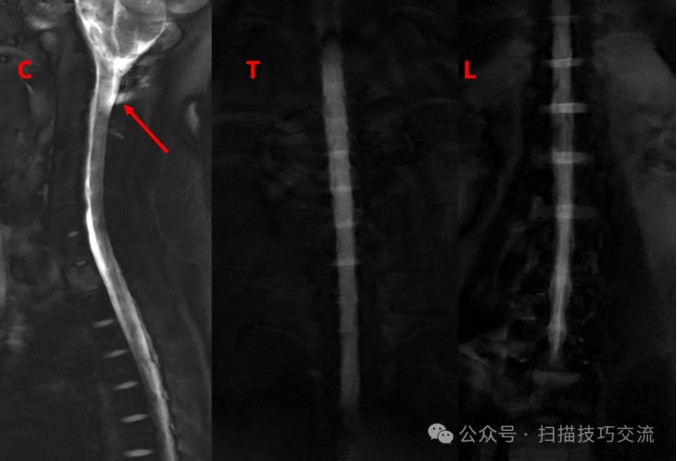

快速的脊髓水成像序列& #40;1s/slice& #41;,试一下,

颈2区域感觉不大对(长箭)。

加个COR 2D MRM对照一下。扫描参数界面: